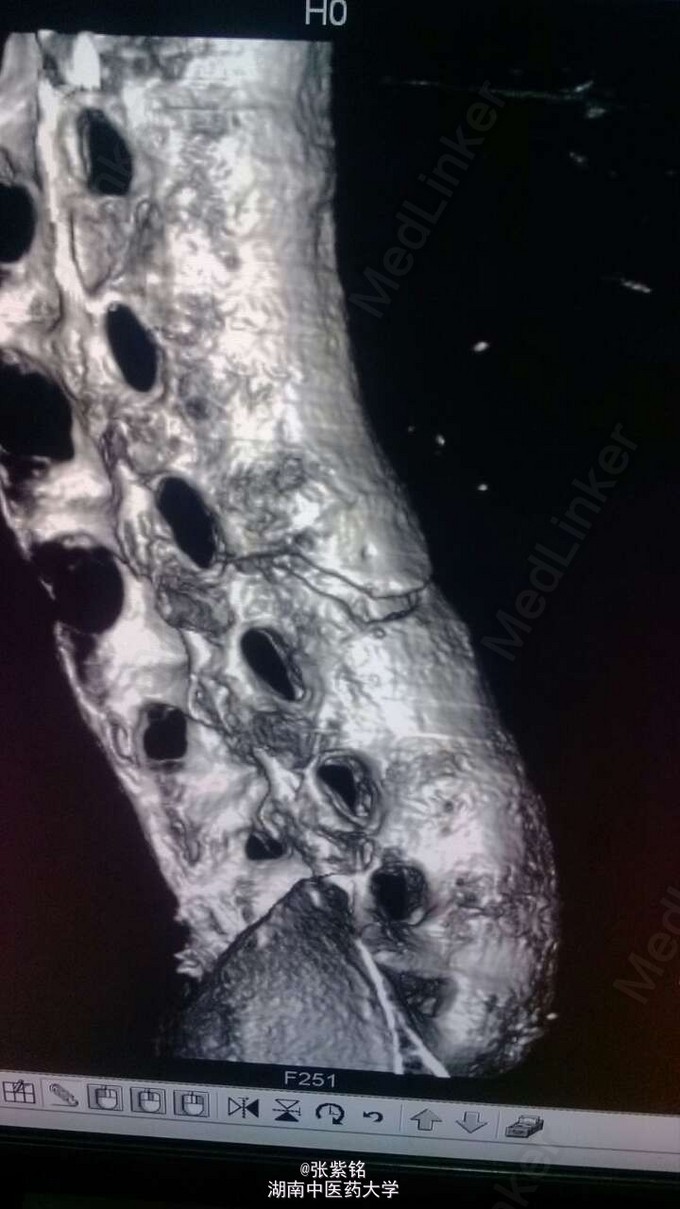

查体见:左额部可见约2cm*2cm皮下血肿,并可见一不规则伤口约2cm,伴活动性出血。脊柱驼背畸形,胸椎后凸,头部前伸体态;颈、腰部旋转活动不能,腰部于L3-5椎体棘突处压痛明显,双下肢肌力、肌张力正常。左肩部关节明显肿胀,可扪及空虚感;局部压痛明显,左Dugas征阳性,左肩关节主动上举,外展,后伸,内收活动受限;被动活动患处疼痛加剧,左侧桡动脉搏动可扪及,皮肤感觉正常,左肘、腕及各指间关节血运感觉活动正常。 X线片示:左肩关节脱位,左肱骨外科颈骨折,左肱骨大结节撕脱性骨折。